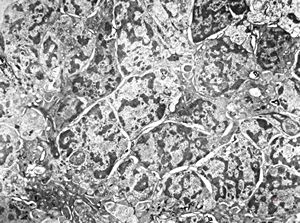

normal kidney - mouse(endothelium and podocytes)

normal kidney - mouse(endothelium and podocyte)